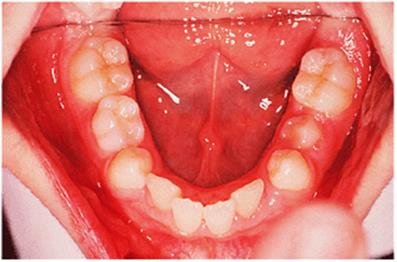

Before discussing functional appliances in detail, Fig. 18.1 gives an overview of this type of functional appliance in clinical use. This patient has a Class II division 1 malocclusion of the type for which functional appliances are very suitable, and for which they have been used for many years.

There are a number of important features to note which will be discussed further later in the chapter. First, the patient is still growing and the signs are that her pattern of facial growth is likely to be favourable. Although the skeletal pattern is Class II, the vertical relationships are close to average and the direction of mandibular growth is likely to be a mild forward rotation (see Chapter 4) which is favourable to the correction of a Class II malocclusion. Second, the soft tissue morphology is favourable despite the lips being incompetent, with the lower lip resting behind the upper incisors. The lower lip line is above the level of the upper incisal edges, and after the overjet has been reduced the lower lip will rest labially to the upper incisors, so helping to resist any tendency for relapse of the overjet. Third, the arches are well aligned — functional appliances have no mechanism for treating irregularities of alignment of the teeth.

Fig. 18.1. (a) This 12-year-old girl had a skeletal II facial pattern and average facial proportions. The lips were incompetent with the lower lip lying below the upper incisors at rest. (b), (c) She had a Class II division 1 malocclusion with an overjet of 10 mm, the overbite was increased and complete, and the molar relationship was Class II on both sides. (d), (e) The upper and lower arches were well aligned. (f) A functional appliance (an activator) was fitted. (g) The corrected occlusion with Class I incisor and molar relationships. (h) The patient's facial profile at the end of treatment.